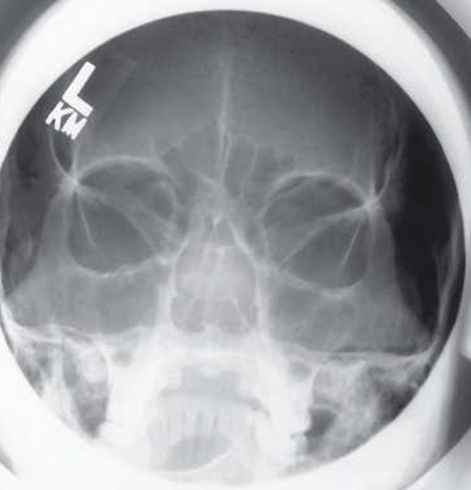

Anatomia Demonstrada

- Assoalhos orbitais (placas) são perpendiculares ao RI, o que também fornece uma perspectiva menos distorcida das margens orbitais que uma incidência parietoacantial (método de Waters).